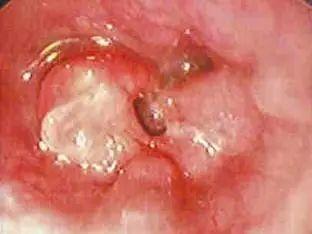

左右滑动查看胃酸侵蚀食道

胃食管反流病长期发作,有可能出现巴雷特食管并发症的可能。巴雷特食管是食管腺癌的癌前病变。

根据数据资料显示,有巴雷特食道者罹癌风险会高出一般人40倍以上。

食道癌变

因此,如果经常有胃食道反流的相应症状,或者察觉自己属高危险人群之一,最好的办法就是:尽早就诊、尽早检查治疗。